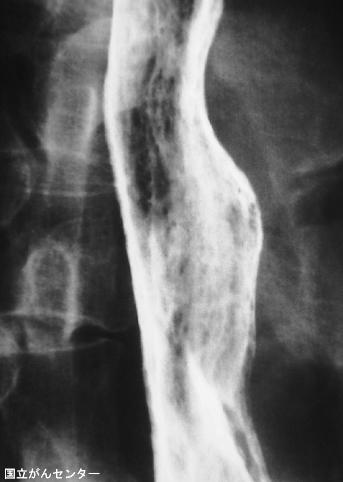

疾患(病理主体)の分類炎症性・潰瘍性疾患/カンジダ食道炎

部位(臓器別)食道/2つ以上

検査方法X-P